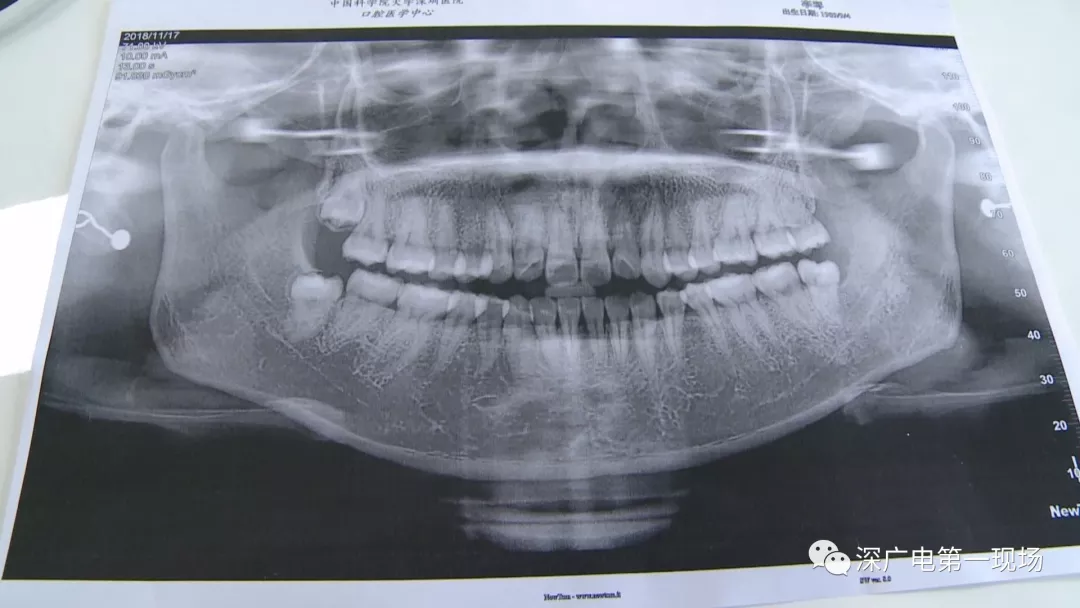

針對(duì)李女士的情況,醫(yī)生介紹,當(dāng)時(shí)要想拔出李女士的這顆智齒,難度還是很大的,屬于復(fù)雜智齒的拔除術(shù)。她的風(fēng)險(xiǎn)在于距離神經(jīng)管近,同時(shí)這顆牙齒完全埋在牙床最后的位置,直接往外拔,會(huì)加大頜骨的風(fēng)險(xiǎn),因此需要先切開(kāi),讓牙齒暴露后,切小再慢慢地拔出。